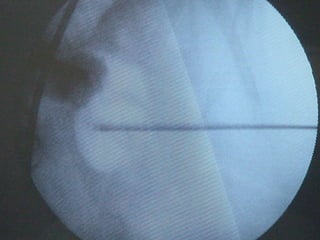

O documento discute o tratamento de urolitíase, especificamente a remoção de cálculos renais através de nefrolitotripsia. A cirurgia aberta é agora muito restrita devido aos avanços da ESWL e procedimentos endourológicos menos invasivos como ureteroscopia e cirurgia percutânea. A cirurgia laparoscópica está substituindo a cirurgia aberta como técnica menos invasiva que combina a tecnologia endourológica com a laparoscópica preservando